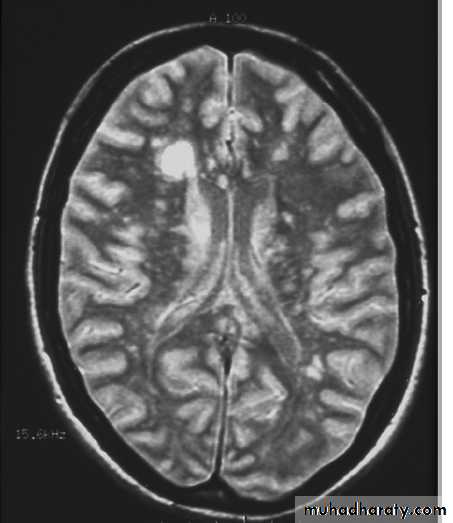

4- MRI brain normal or lesions not that area of ms like in area postrema of medulla ,hypothalamus …

--Clinically some manifestation mimic MS but associted with encephalopathy (confusion ,drowsiness)--MRI brain show demylinating plaques differ from that of MS plaques by it is larger, confluent, affect white and gray mater(basal ganglia and thalamus) and sotimes it is symetrical with contrast enhacement